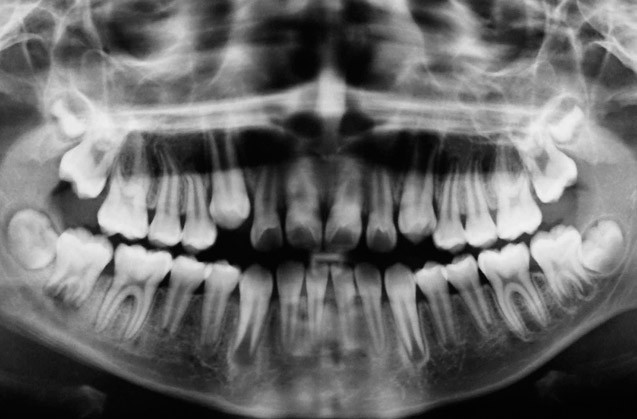

Radiografía dental

Las radiografías dentales son un tipo de imagen de los dientes y la boca. Los rayos X son una forma de radiación electromagnética de alta energía y penetran el cuerpo para formar una imagen en una película o en una pantalla. Las radiografías pueden tomarse de manera digital o en una película, son un método muy útil para identificar problemas dentales que no se perciben a simple vista.